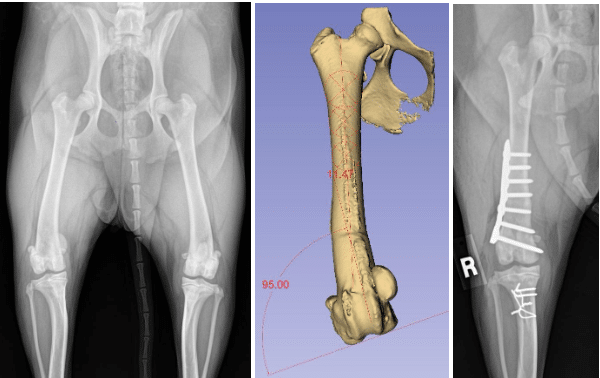

The radiograph (X-ray) to the left shows a dog with a severe bowlegged deformity and patella luxation.

In these dogs, the solution to the patella luxation involves straightening the thigh bone (femur) by cutting the femur, removing a wedge section, and then securing the femur back together with a bone plate and screws. The bone then heals over the next 10-12 weeks. The bone plate and screws could be removed, but are almost always left in place.

The radiograph (X-ray) image below left shows a dog with patella luxation affecting the right knee (stifle). This patient has about 11° of extra curvature to the femur. The center image below shows the three-dimensional (3D) model of that dog’s bowlegged right femur and measurements of the curvature. The radiograph (X-ray) below right shows the dog’s femur immediately following surgery in which the femur has been cute and bone plate and screws have been used to straighten the dog’s femur.